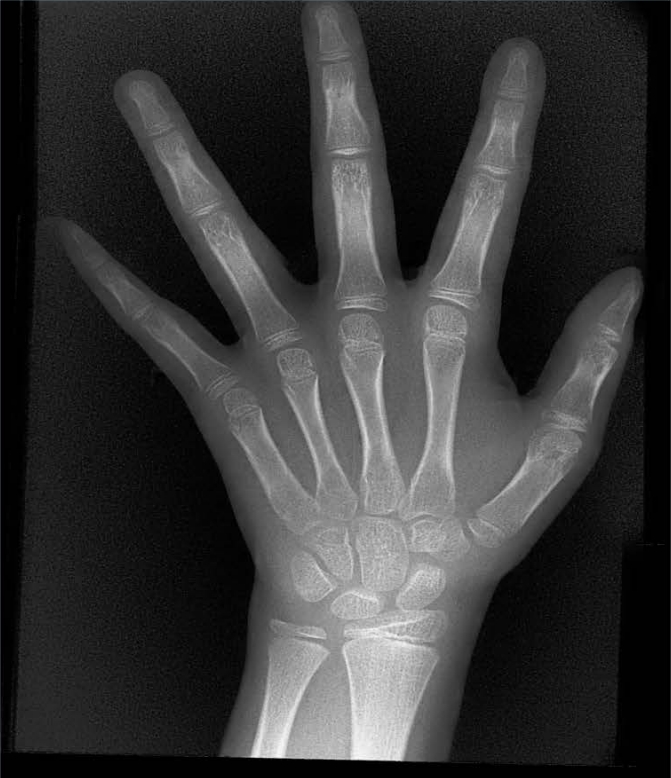

X射線骨齡儀通過拍攝兒童手腕部(指骨、掌骨、腕骨)的X射線影像,依據(jù)骨骼的形態(tài)、大小、鈣化程度等特征,結(jié)合評(píng)估標(biāo)準(zhǔn)(如《中國青少年兒童手腕骨成熟度及評(píng)價(jià)方法》,簡稱《中華-05》標(biāo)準(zhǔn))進(jìn)行骨齡判定。相較于傳統(tǒng)檢測(cè)方式,X射線骨齡儀具有輻射劑量低、影像清晰度高、檢測(cè)效率高的優(yōu)勢(shì),能精準(zhǔn)捕捉骨骼發(fā)育的細(xì)微變化,為骨齡評(píng)估的準(zhǔn)確性提供保障。